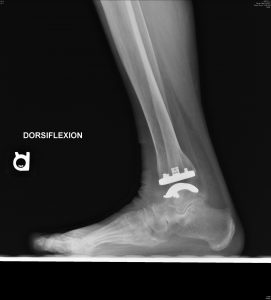

Follow-up is too short at this point to report outcomes for the Vantage. However, my colleagues and I have been collecting data on every Vantage that we implant, including validated patient-reported outcomes, accepted objective outcomes measures and standardized radiographic evaluations. (Fig 10 A and B) To date, our observations reflect high patient satisfaction, low complication rates and a trend toward favorable range of motion confirmed with objective postoperative radiographic dorsiflexion and plantarflexion measurements. While my colleagues and I initially limited the Vantage to end-stage ankle arthritis with minimal deformity, more recently we expanded indications to include varus and valgus ankle arthritis. At early follow-up our results are equally favorable for end-stage ankle arthritis with and without deformity.